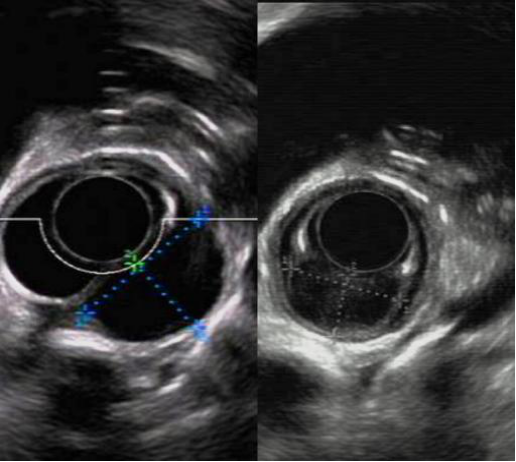

在朋友的推荐下,杨先生来到哈医大一院,经过腔镜肿瘤外科李军教授,消化内科徐洪雨教授及胸外科姜久仰教授等多学科专家会诊。徐洪雨通过超声内镜检查,提出“可以尝试通过内镜黏膜下隧道技术切除肿瘤,而且可以通过一条隧道切除两个肿物”的手术方案。

内镜下经隧道肿物切除术(STER)创造性地巧妙利用消化道黏膜和固有肌层之间的空间建立“隧道”进行操作,创伤小,术后无体表疤痕,既能充分体现“微创治疗”的优越性,更因术后患者恢复快,住院时间短,治疗费用低,可以大大减轻患者的家庭负担和医保资源。同时,徐洪雨分析患者食管肿物位于食管中上段固有肌层,直径为2.5cm,突向纵膈生长,比邻气管及胸主动脉,术中出现气胸、纵膈气肿、气腹、出血的风险较大,更存在切除第一个肿物后出现气胸而无法切除第二个肿物的后续风险。

徐洪雨和李军联合为患者实施手术。徐洪雨在张蕾护士的配合下在内镜下距患者门齿22cm处建立黏膜下隧道,显露肿物,依次完整剥离两个肿物,切除肿物,关闭隧道入口,食管粘膜完整无破损。术中零出血、无气胸,患者清醒后仅有胸骨后及咽部轻度不适,可自由行动,三天后就可以进流食,目前患者恢复良好,已治愈出院。